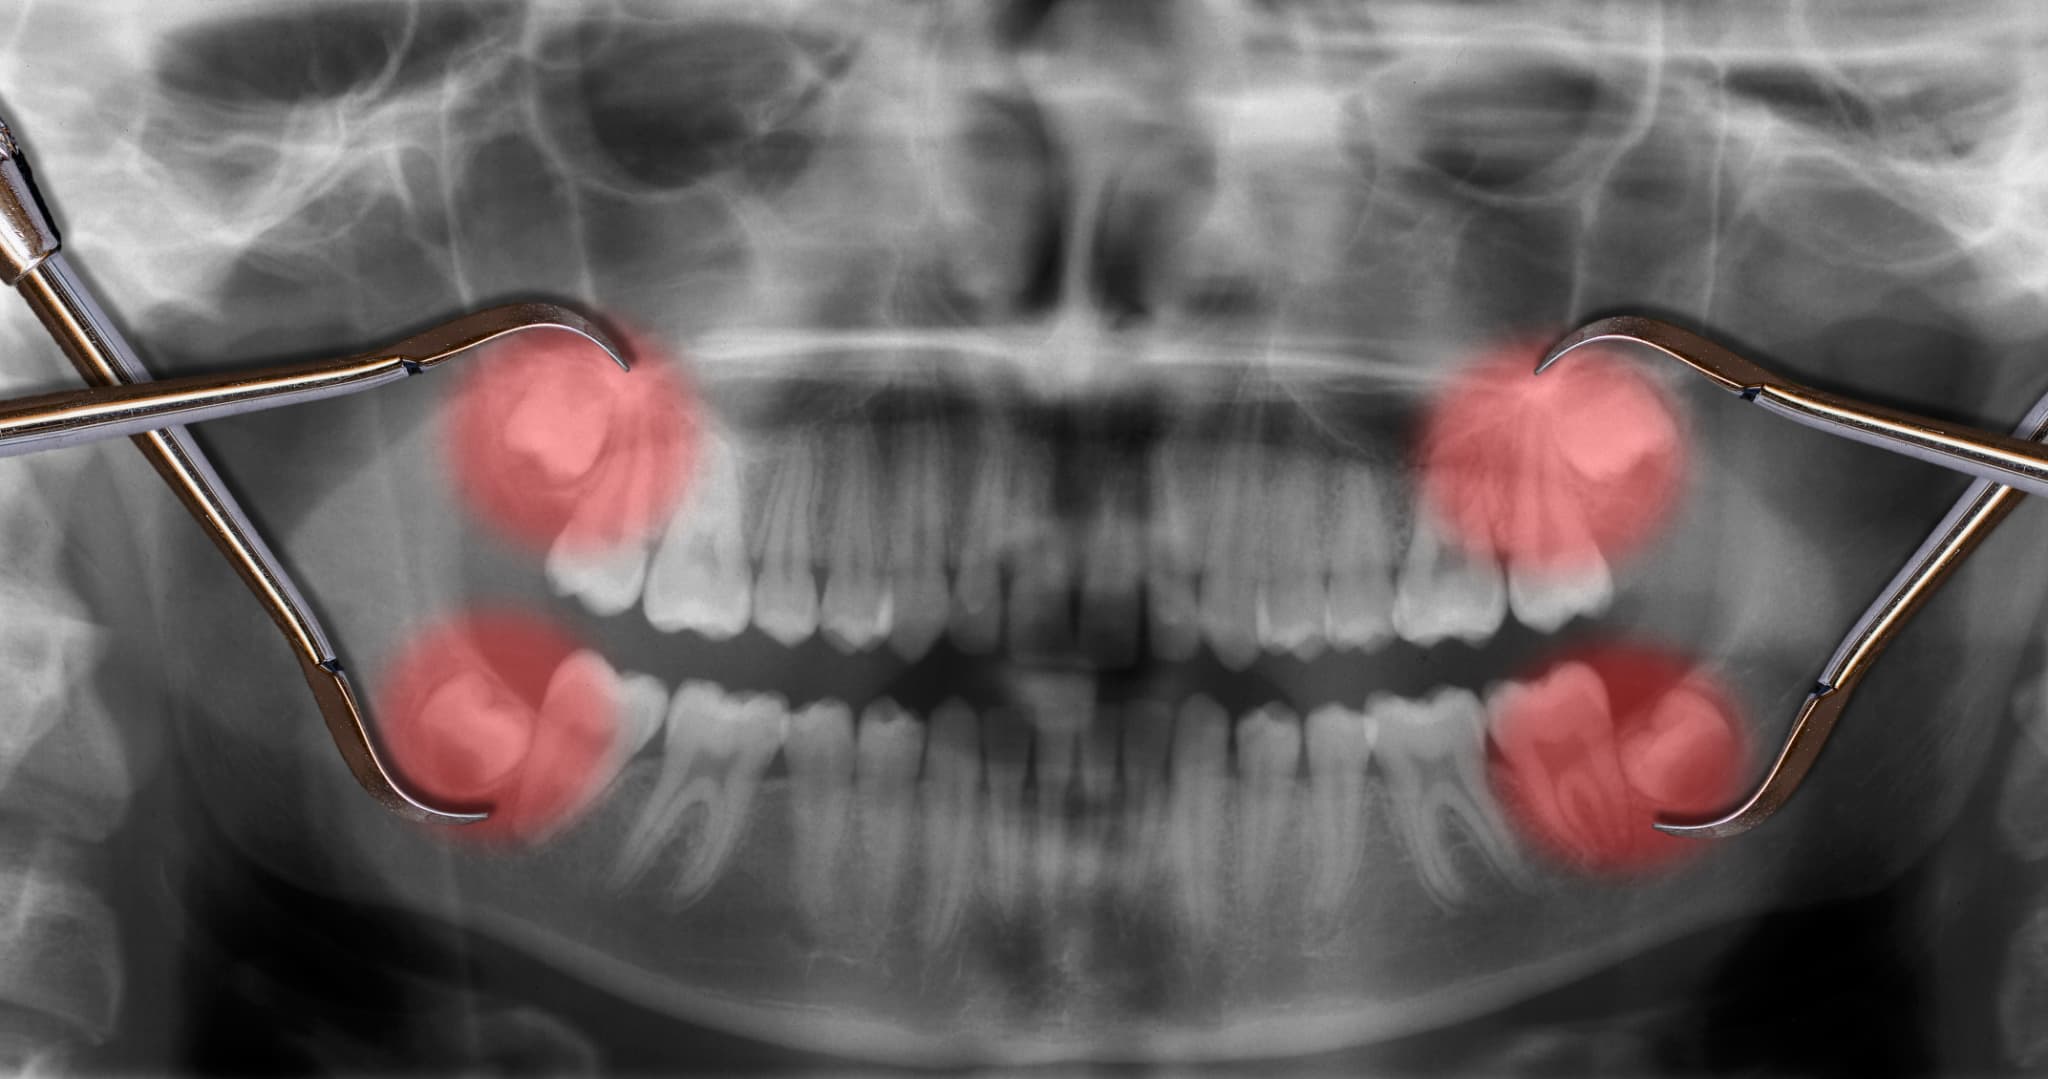

嚢胞

嚢胞(のうほう)とは、あごの骨の中にできる液体がたまった袋のようなものです。埋まったままの親知らずのまわりに発生することがあり、初期には痛みがないこともありますが、だんだん大きくなると骨を圧迫して痛みや違和感が出てきます。

レントゲンで見つかることが多いため、歯科医院で定期的に検査を受けることが大切です。嚢胞ができた場合は、外科的に取り除く処置が必要になります。

一方で、親知らずが斜めや横向きに生えている場合、隣の歯を圧迫していたり、炎症や虫歯を繰り返していたりすると、抜歯を検討することになります。

放置すると、周囲の歯や骨にも影響を及ぼすおそれがあるため、歯科医院でレントゲン撮影をし、詳しく状態を確認したうえで判断することが大切です。自己判断は避け、歯科医師のアドバイスを受けるようにしましょう。